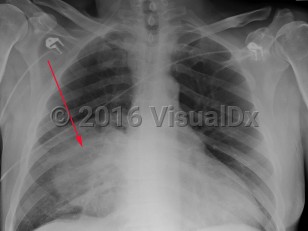

Streptococcus pneumoniae pneumonia

Streptococcus pneumoniae (pneumococcus), an encapsulated aerobic gram-positive diplococcus, is the most common cause of community-acquired pneumonia in adults. Ninety different serotypes have been identified based on antigenic differences in their capsular polysaccharides.

Pneumococcal pneumonia often starts as a single shaking chill. Fevers, cough with sputum, fatigue, and chest pain are common symptoms. Fever may be absent in elderly patients. Examination may reveal crackles on the affected side and signs of consolidation, like dullness to percussion and tubular breath sounds. Also present may be signs of a pleural effusion. Any new heart murmur should raise the suspicion for endocarditis. Otitis media, sinusitis, meningitis, and endocarditis are the other manifestations of pneumococcal infection.